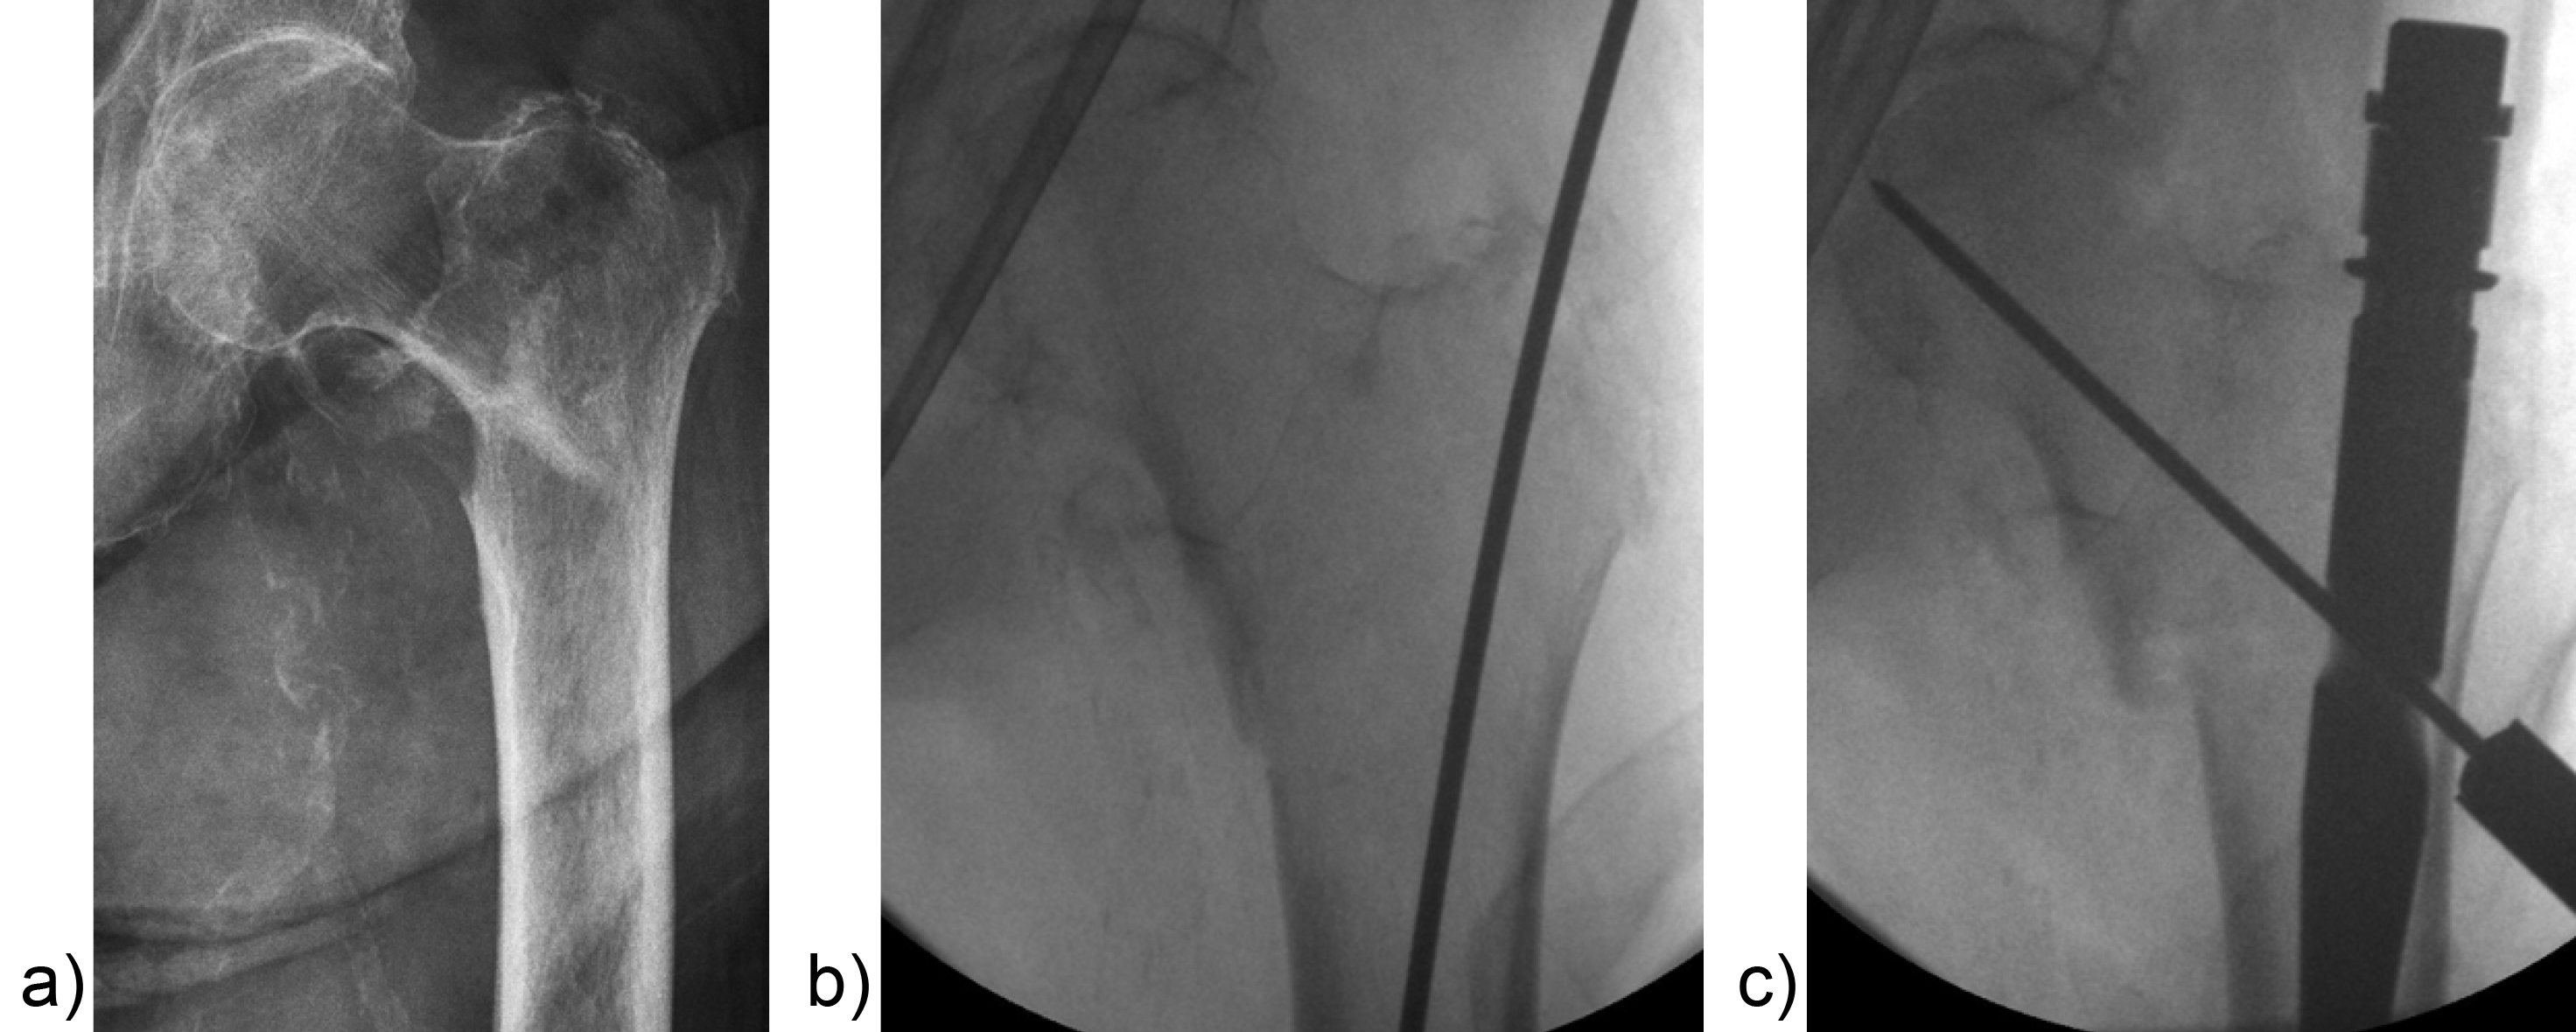

Surgeons often report some loss of reduction during nail insertion, specifically in cases involving nail insertion through a fractured greater trochanter. This often leads to an unintended varisation of the head-neck fragment (HNF) and a medialization of the HNF resulting in reduced bone contact in the calcar area (Fig 2 and 3).

The combination of a large proximal nail diameter and a very lateral entry point has been identified as a potential reason for such a loss of reduction. As a result, a smaller diameter nail with a laterally flattened profile to more appropriately respect the anatomy of the proximal lateral femoral wall would be advantageous. Both design features have been realized with the new nail. The smaller 15.66 mm proximal nail diameter of the TFNA (compared to 16.5 mm and 17 mm for PFNA/PFNA-II and TFN) and the LATERAL RELIEF CUT design (Fig 4) of the proximal nail end serve to reduce the potential impingement of the nail with the lateral femoral wall and the HNF. Both of these issues could result in varus malalignment and a loss of reduction, which remain key indicators for an increased risk of cut-out. The small proximal nail diameter also helps to preserve bone in the insertion area, which is especially beneficial in the femora of small stature patients.

Features to avoid suboptimal placement of the head element

Apart from the newly introduced nail design features, which help to maintain a good reduction, it is also essential to place the head element in the correct position of the femoral head to avoid cut-out or cut-through. Numerous studies have demonstrated that a center/center position of the head element ensures the best clinical outcome. Multiple instrument features, including a multi hole drill sleeve for the facilitation of precise nail entry and aiming aids to accommodate the placement of the head element guide wire in the correct position have been added to the TFNA system to enable accurate implant placement. The insertion handle is radiolucent and has radiographic indicators to help the surgeon with exact guide wire placement for head element positioning in the lateral view (Fig 5). This feature, together with the guide wire aiming device, which checks guide wire position in the AP view, is influential in the placement of the guide wire in the center/center position of the femoral head. It also helps to reduce the number of imaging maneuvers and x-ray shots required.